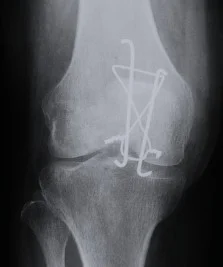

| Tension Band Wires | Special mechanics in – Patella – Olecranon – Malleolar fractures | ![]() |